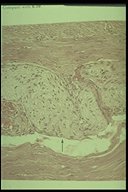

Only thick nerve fiber is demonstrated without ganglion cell in Hirschsprung's disease